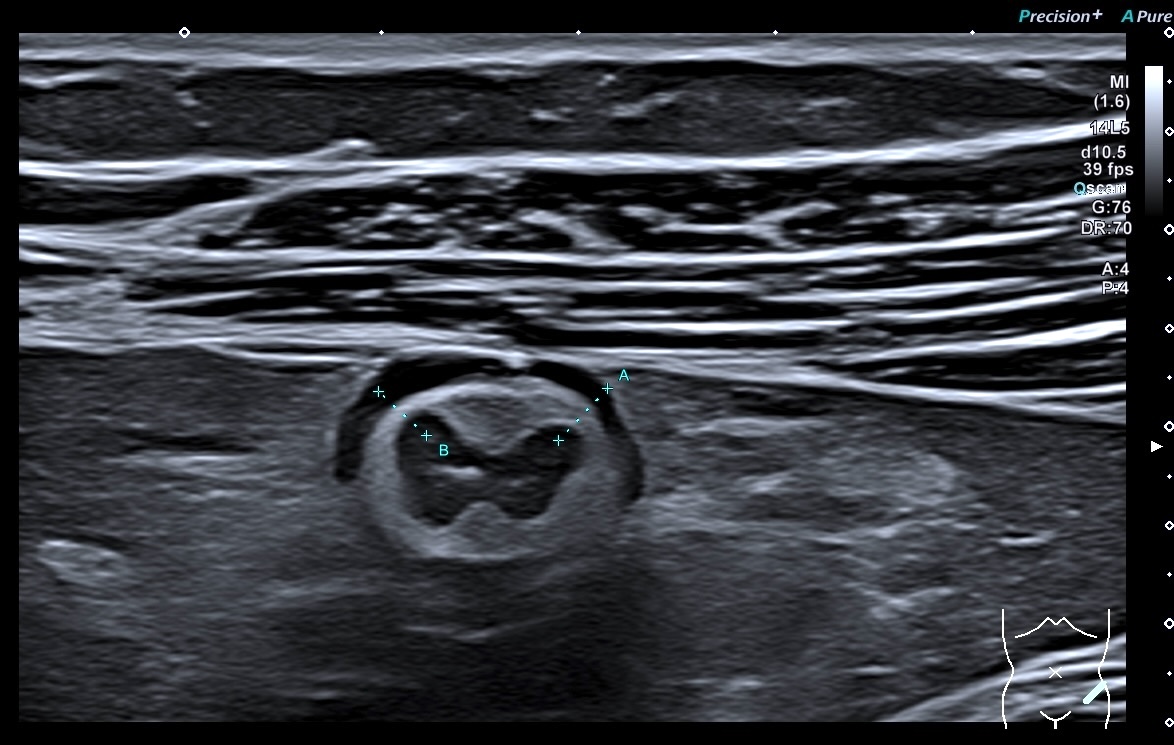

Sigmoïde coupes transversales et longitudinales haute fréquence

Ci-dessus, images de la paroi du sigmoïde avec la sonde haute fréquence. On a toujours les mêmes caractéristiques

La graisse est peu infiltrée, Doppler plus marqué (Limberg 2 voir 3)

Le score de Milan est de (4,5 x 1,4+2)= 8,3 donc la maladie reste active, elle s'est même dégradée. (Score passé de 5.74 à 8.3)